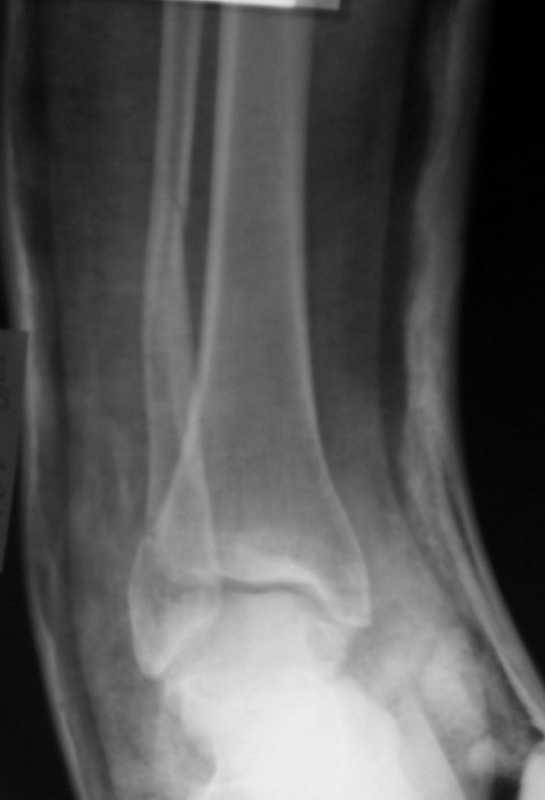

Вот рентгенконтроль на 7-е сутки после репозиции.

Серега, привет! А что наш ув.доцент А.П.М. говорит по этому поводу. И вообще, я не знал, что ты лечишь 3-хлодыжечные задними лонгетами, - нас с тобой учили это делать циркулярными гипсовыми повязками. Все равно, удачи! На контроле, почему-то, все заманчиво хорошо. Не спеши делать выводы

Стандартными снимками считается прямая, боковая и мортиз!!!, а так трудно гадать, насколько потеря длины малоберцовой. На боковом снимке не сопоставленный перелом медиальной лодыжки и перелом заднего края без смещения.

Вероятность ошибки при оценке состояние сустава без стандартных снимков возрастает на 30%, поэтому необходимо добиться от рентгенолога всех необходимых снимков.